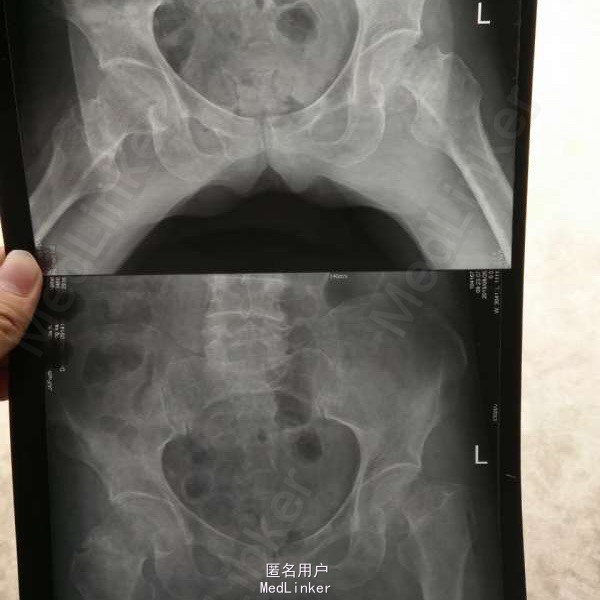

双侧髋部骨折一例

女,52岁,跌伤致双侧髋部疼痛活动受限1天。左股骨颈骨折,右粗隆间骨折。